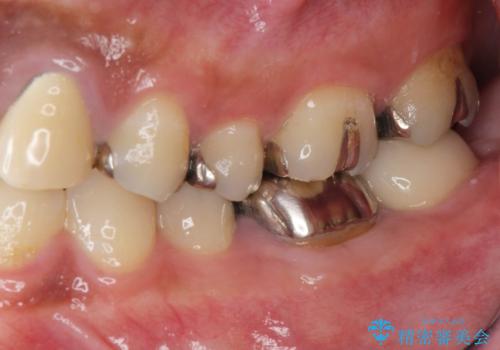

- 長年虫歯の治療を受け続けたことで銀歯・コンポジットレジン修復だらけになってしまい、今後の見た目や歯を大切にするためにセラミック治療矯正治療を希望され来院されました。

マイクロスコープを用いた精密根管治療やセラミック治療、マウスピース矯正治療を一つの医院で行うことのできる当法人ならではの総合歯科治療を実践していきます。

歯並びを整えたことで、歯ブラシのしやすさが向上し見た目も銀歯を全て除去したことで大きく改善して大変満足いただくことができました。